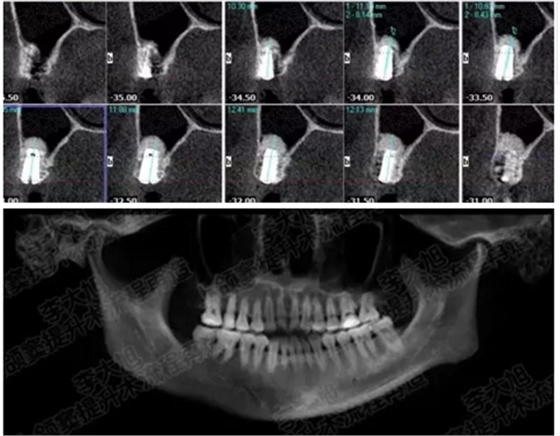

病例四

剩余骨量2mm-5mm且存在斜形竇底

007.png

提升8mm

008.png

009.png